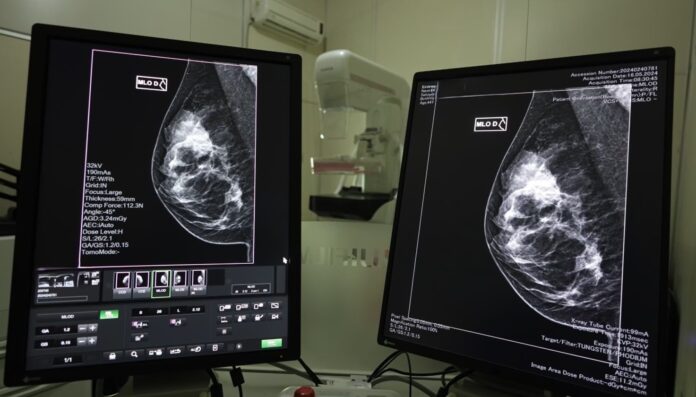

Governo de SC lança mutirão de mamografias no mês da Mulher

Demais unidades vinculadas à pasta realizarão ações de cuidado à saúde da mulher também neste mês de março

No mês em que é comemorado o Dia Internacional da Mulher, a Secretaria de Estado da Saúde (SES) chama a atenção sobre as doenças que acometem o sexo feminino, entre elas o câncer de mama. Como parte das ações do Governo de Santa Catarina neste mês, a Maternidade Carmela Dutra, em Florianópolis, e o Hospital Regional Terezinha Gaio Basso, em São Miguel do Oeste, irão promover mutirão de mamografias em pacientes que aguardam no Sistema Nacional de Regulação (Sisreg). Demais unidades vinculadas à pasta realizarão ações de cuidado à saúde da mulher também neste mês de março.

“Neste mês estamos buscando reforçar ações de prevenção da saúde da mulher nas unidades da Secretaria de Estado da Saúde. O câncer de mama é a neoplasia que mais afeta as mulheres no mundo e quando o diagnóstico é precoce, as chances de cura são muito maiores. Por orientação do governador Jorginho Mello, estamos atuando para enfrentar a fila de mamografias ampliando a oferta desses exames nas unidades próprias e  repassando recursos para os consórcios intermunicipais de saúde a fim de ampliar a oferta deste serviço. Quem tem câncer, tem pressa”, destaca o secretário de Estado da Saúde, Diogo Demarchi Silva.

Em 2024, mais de 2,5 mil mulheres receberam o diagnóstico de câncer de mama e 167,2 mil mamografias foram realizadas pelo Sistema Único de Saúde (SUS). Além disso, as unidades habilitadas em oncologia realizaram 613 cirurgias desta neoplasia no ano passado.

A detecção precoce do câncer de mama é fundamental para aumentar as chances de tratamentos menos invasivos e com maiores taxas de sucesso. As mamografias são realizadas pelo SUS, via Atenção Primária à Saúde, com prestadores dos municípios e Consórcios de Saúde. Hospitais de gestão estadual que prestam serviços de saúde da mulher e possuem mamógrafos também realizam os exames.